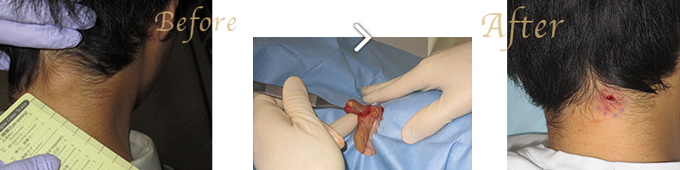

当院ではくりぬき法もやっています。

くりぬき法とは、小切開で写真のように小さな穴から取り出すので傷跡が小さく済みます。

但し既往の炎症の有無などによって、適応できない場合がありますが、いずれにしても最善の方法を提案いたします。

施術方法:診察での診断と症状により異なりますが、粉瘤(アテローム)の場合、落ち着いて形状が安定していれば手術で袋を取り除きます。